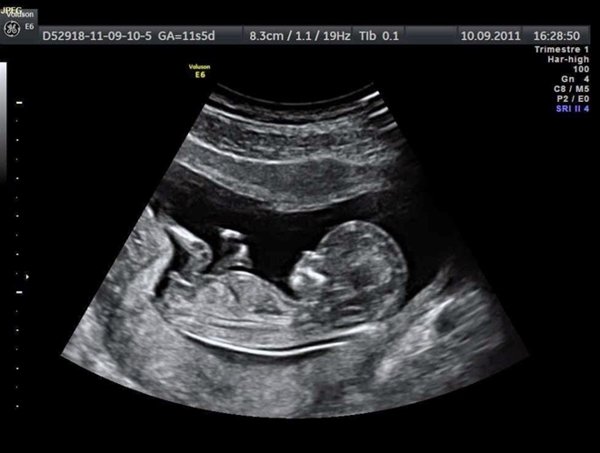

Siêu âm: Chẩn đoán thai chậm tăng trưởng (TCTT) cần phải siêu âm đo đạc kích thước thai ít nhất 2 thời điểm, cách nhau ít nhất 4 tuần. Chẩn đoán thai chậm phát triển trong tử cung dựa chủ yếu vào siêu âm do thường không có triệu chứng đặc trưng. Tuy nhiên, có một số dấu hiệu thai chậm phát triển trong tử cung gợi ý như:

Việc xác định chính xác tuổi thai dựa vào siêu âm 3 tháng đầu giữ vai trò then chốt. Các chỉ số sinh học AC < 10% giúp phát hiện TCTT với tỷ lệ 75%, vòng bụng nhỏ là một dấu chứng nhạy để phát hiện TCTT. Để chẩn đoán xác định cần dựa vào siêu âm là chủ yếu vì:

Đây là phương pháp hữu hiệu để chẩn đoán vì có thể so sánh đối chiếu kích thước của thai với kích thước chuẩn từ đó đánh giá thai chậm phát triển trong tử cung cân đối hay không cân đối

Có đến 90% trường hợp thai chậm phát triển trong tử cung có thiểu ối và dễ dàng phát hiện được qua siêu âm

Có khả năng ước lượng được trọng lượng thai để đối chiếu với chỉ số trung bình